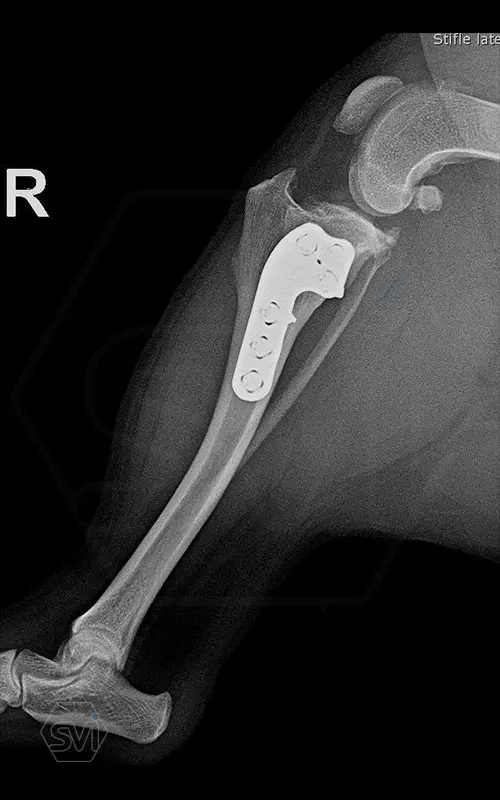

The cranial cruciate ligament rupture of a 7-year-old 8 kg active mix dog was solved a year ago with a precontured polyaxial 2.4mm system, now the other leg has been laid out, and this plate was used here as well. The stability of the system, its fit to the bone and the good healing can be measured nicely on the 1-year control X-ray.

The 2.4 system is great to use where the 2.0mm is already small, but the 2.7mm is still very big. This is a populous family of 6-14 kg dogs, according to our own data for 2021, the 2.4 mm size makes up 14% of all TPLO surgeries!